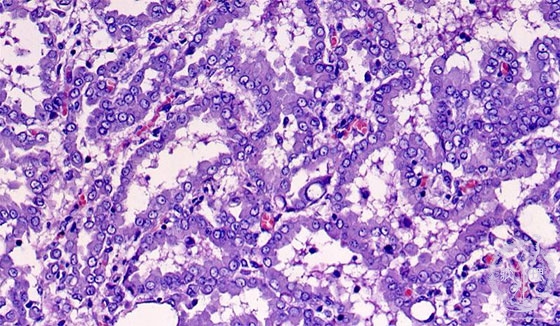

Microscopic view (HE stain, high power view): Mesothelioma cells have round nuclei and eosinophilic cytoplasm. Differentiation from lung adenocarcinoma is sometimes difficult.